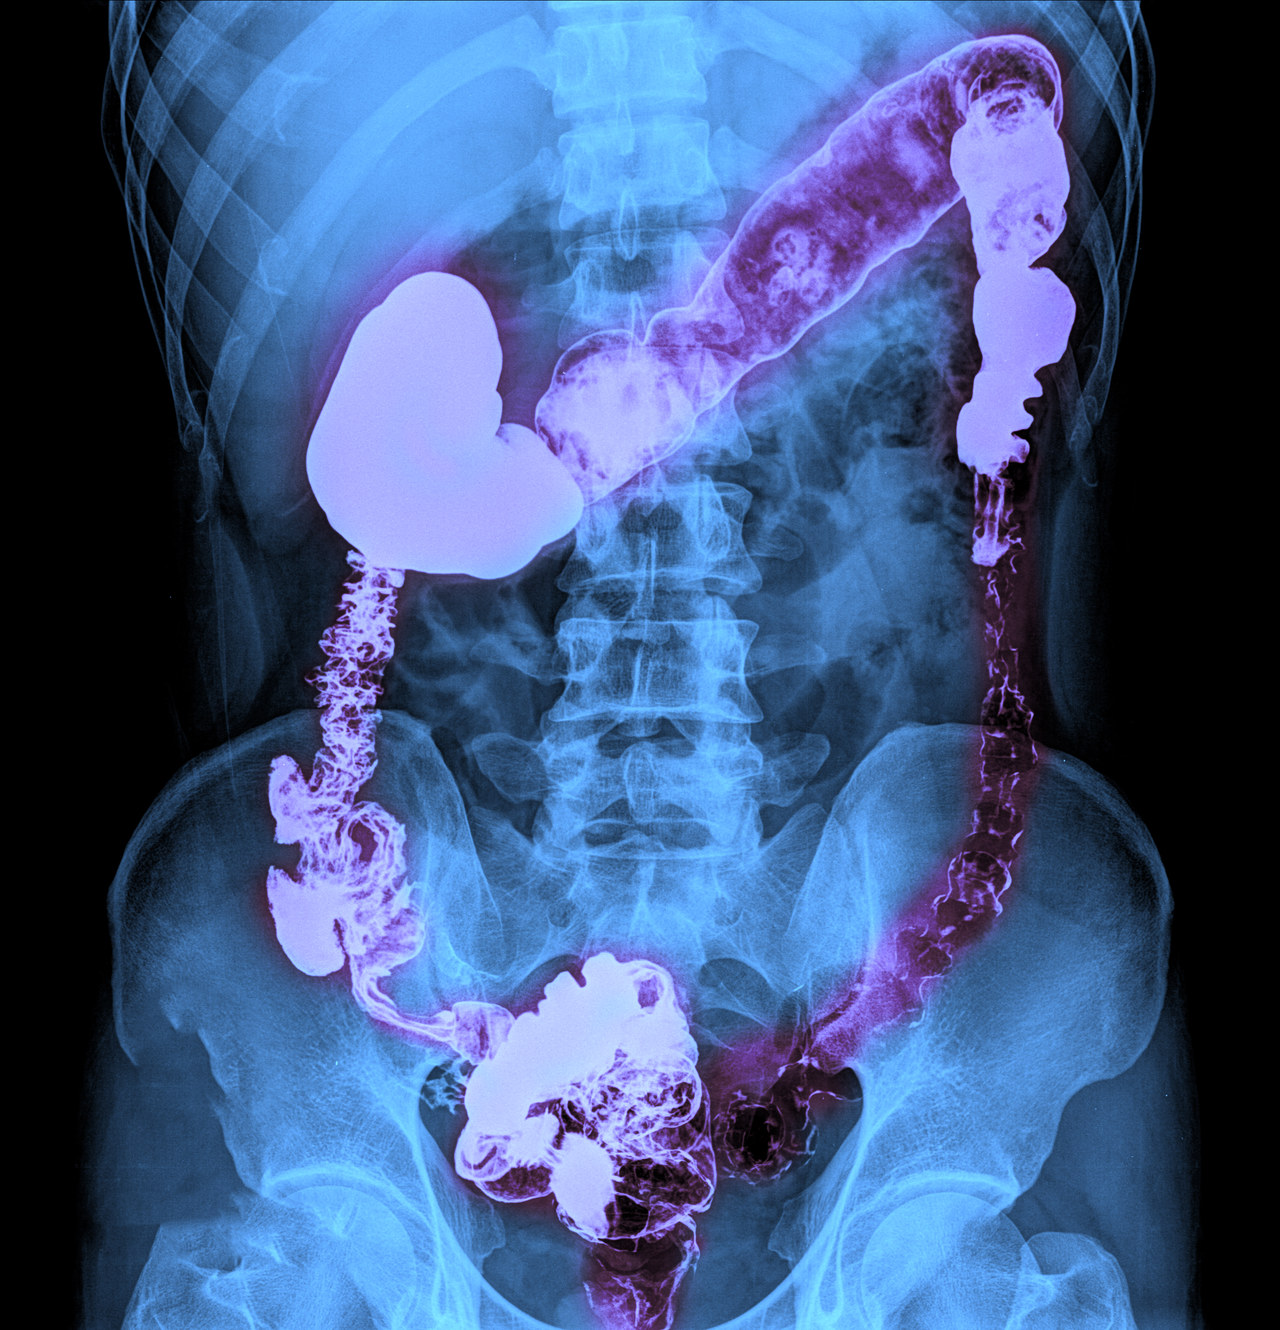

结肠恶变饮食要注意什么

结肠恶变(结肠癌)患者在饮食方面需要特别注意,合理的饮食可以帮助缓解症状、促进康复,甚至对疾病的预防和治疗起到辅助作用。